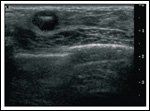

A 30-year-old female at 6 weeks’ gestation of a highly desired pregnancy presented to our multidisciplinary breast cancer clinic with a new diagnosis of invasive ductal carcinoma of the right breast. The patient had just become aware of her pregnant state when she noted a mass in her right breast on self-examination. She was evaluated with a diagnostic mammogram with proper shielding and an ultrasound, confirming a 1.4-cm solid mass corresponding to the palpable lesion (Figures 1 and 2). Ultrasound-guided core needle biopsy was obtained and revealed a grade 3/3 invasive ductal carcinoma, estrogen receptor (ER)-negative, progesterone receptor (PR)-negative, and human epidermal growth factor receptor 2 (HER2)-negative. On physical exam, she showed changes to the breast tissue consistent with early pregnancy, a palpable mass at the biopsy site, and no axillary adenopathy or contralateral findings. The remainder of her examination was likewise benign.

Diagnostic MammogramFIGURE 2

Ultrasound ConfirmationTABLE 1

Dr. Jennifer Diamond: Ultrasound is ideal in evaluating a breast mass during pregnancy as it poses no risk to the fetus and has a sensitivity for malignancy approaching 100%.[1-3] Mammography also poses little risk to the fetus and is considered to be a safe imaging technique in pregnancy if necessary. The dose of radiation to the fetus with a standard bilateral mammography using abdominal shielding has been estimated at 0.004 Gy of radiation, falling well below the threshold for malformation in the fetus of 0.05 Gy of radiation.[4] The earlier in pregnancy, the lower the exposure to the fetus.